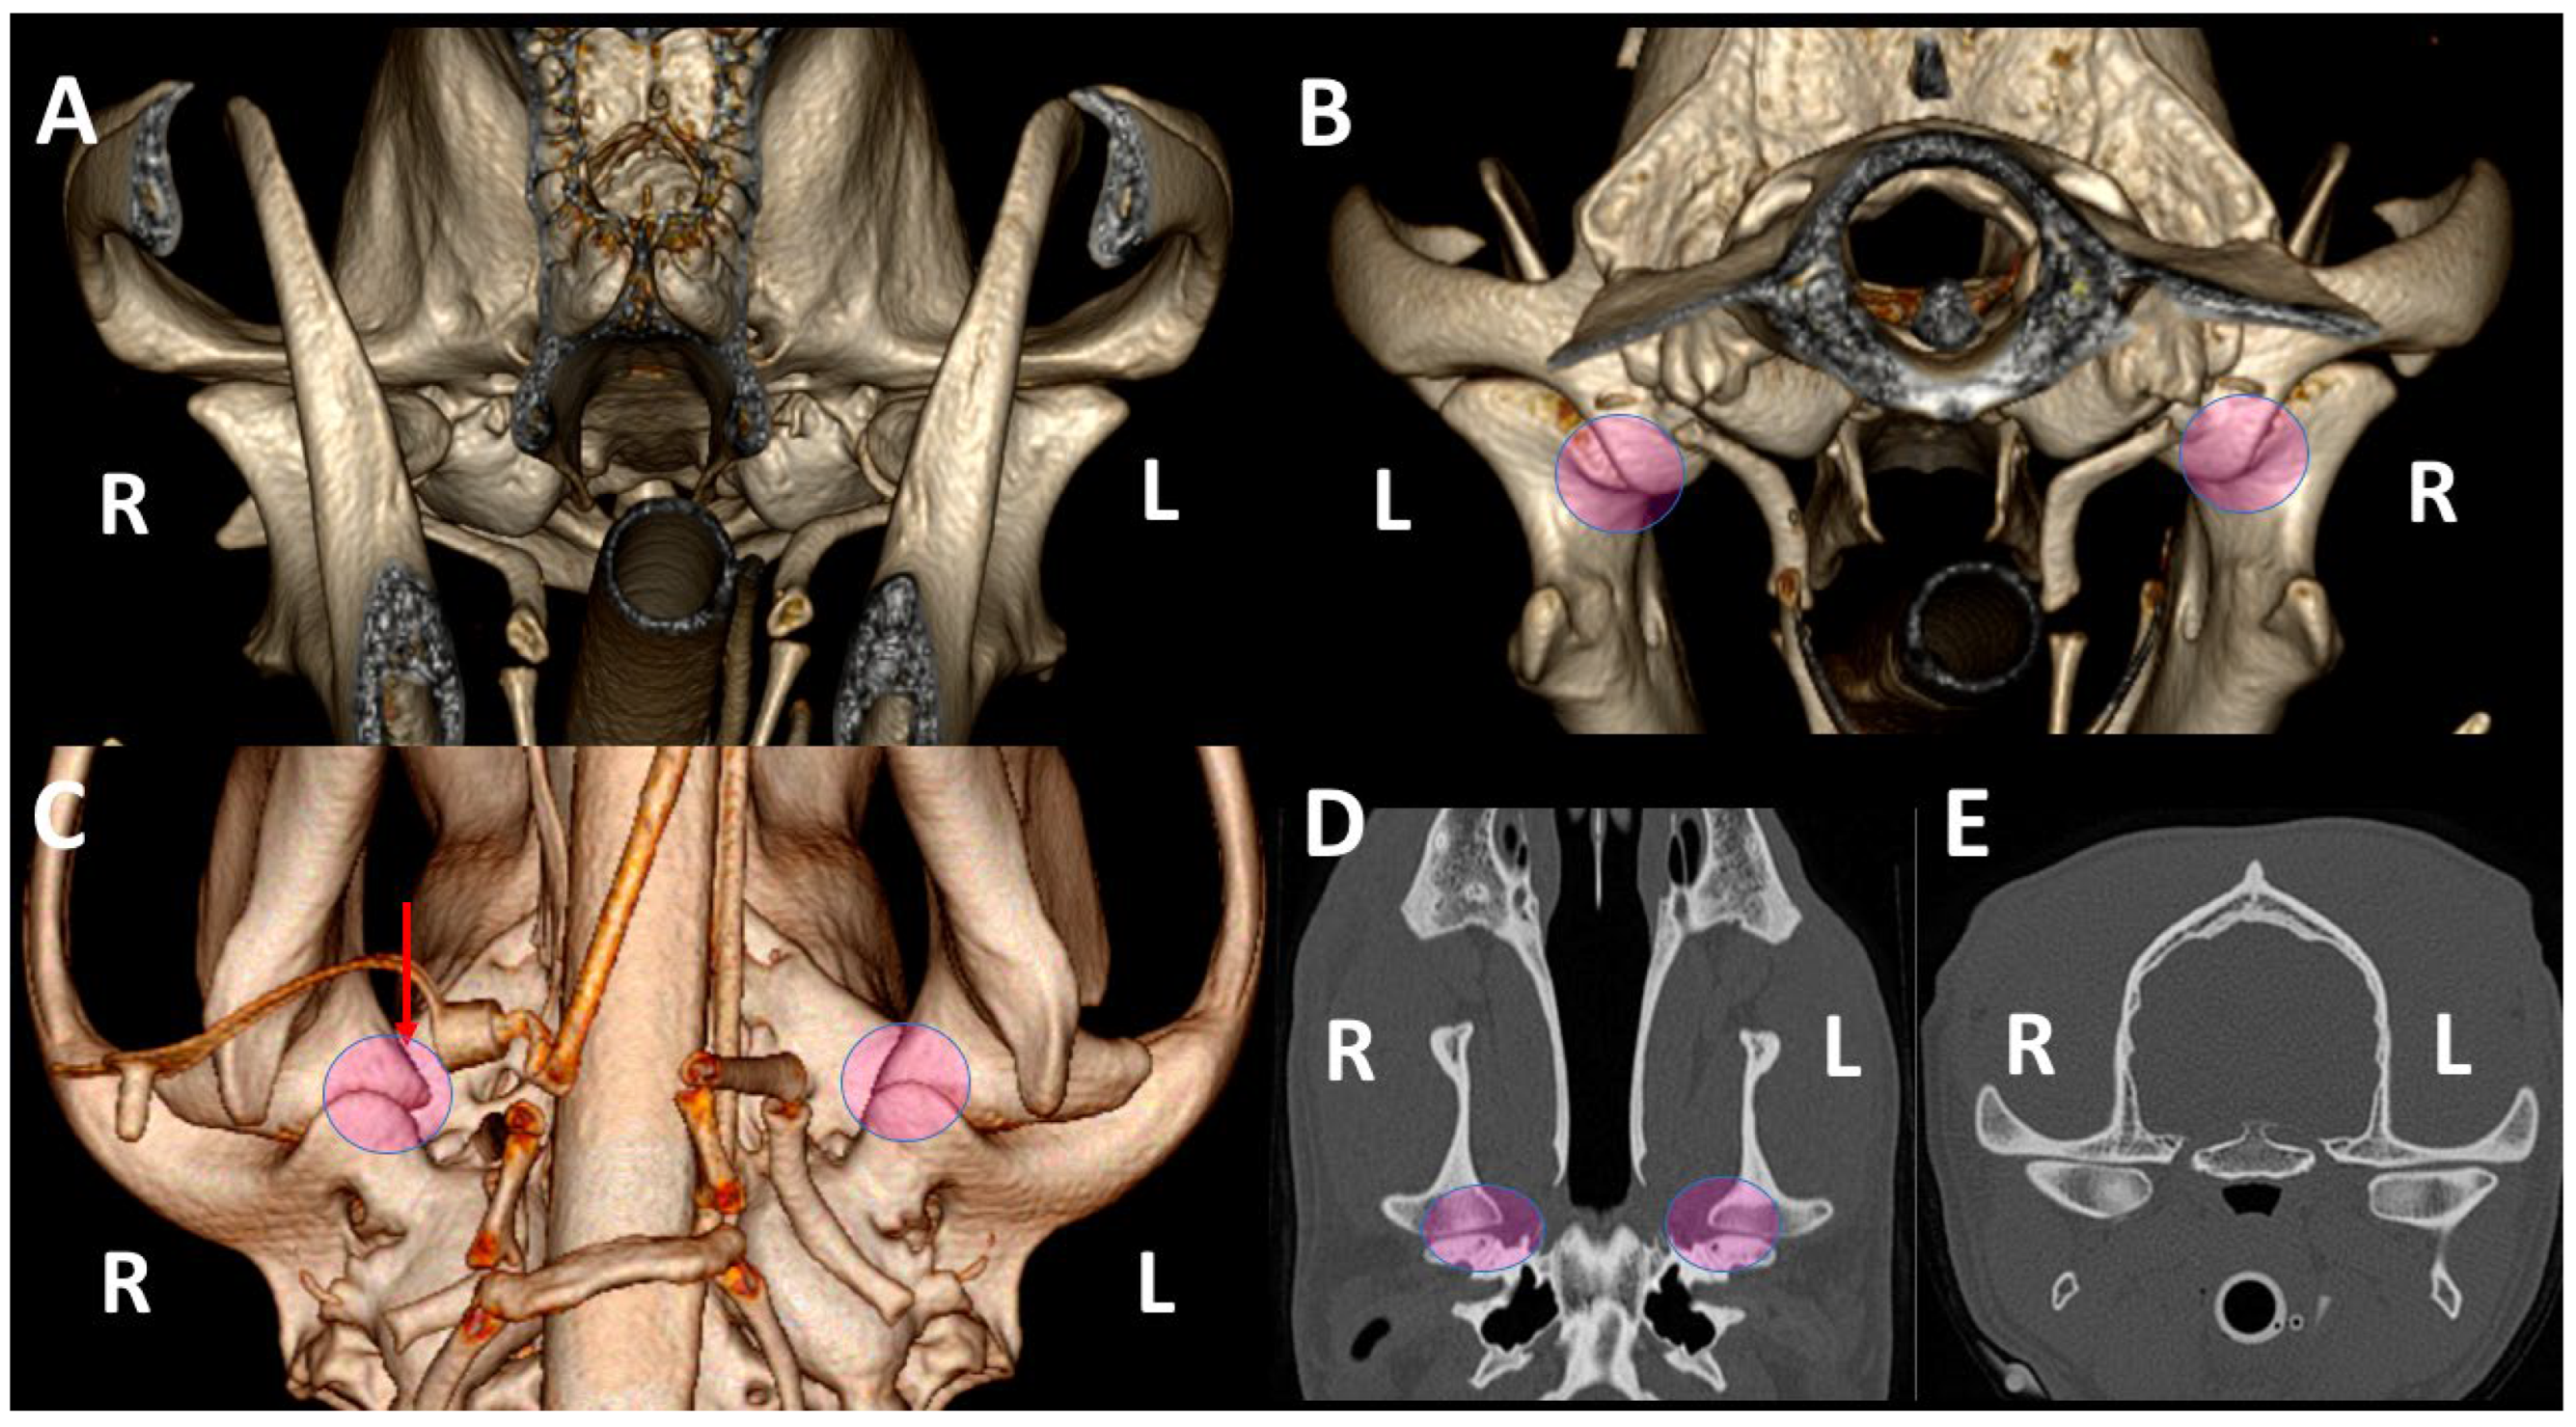

3.3. A Detailed Assessment of Each TMJ Comparing 3DVR Images with the Three Standard CT Planes

3.4. A Pictorial Essay of 3DVR Images in Some Pathological Cases